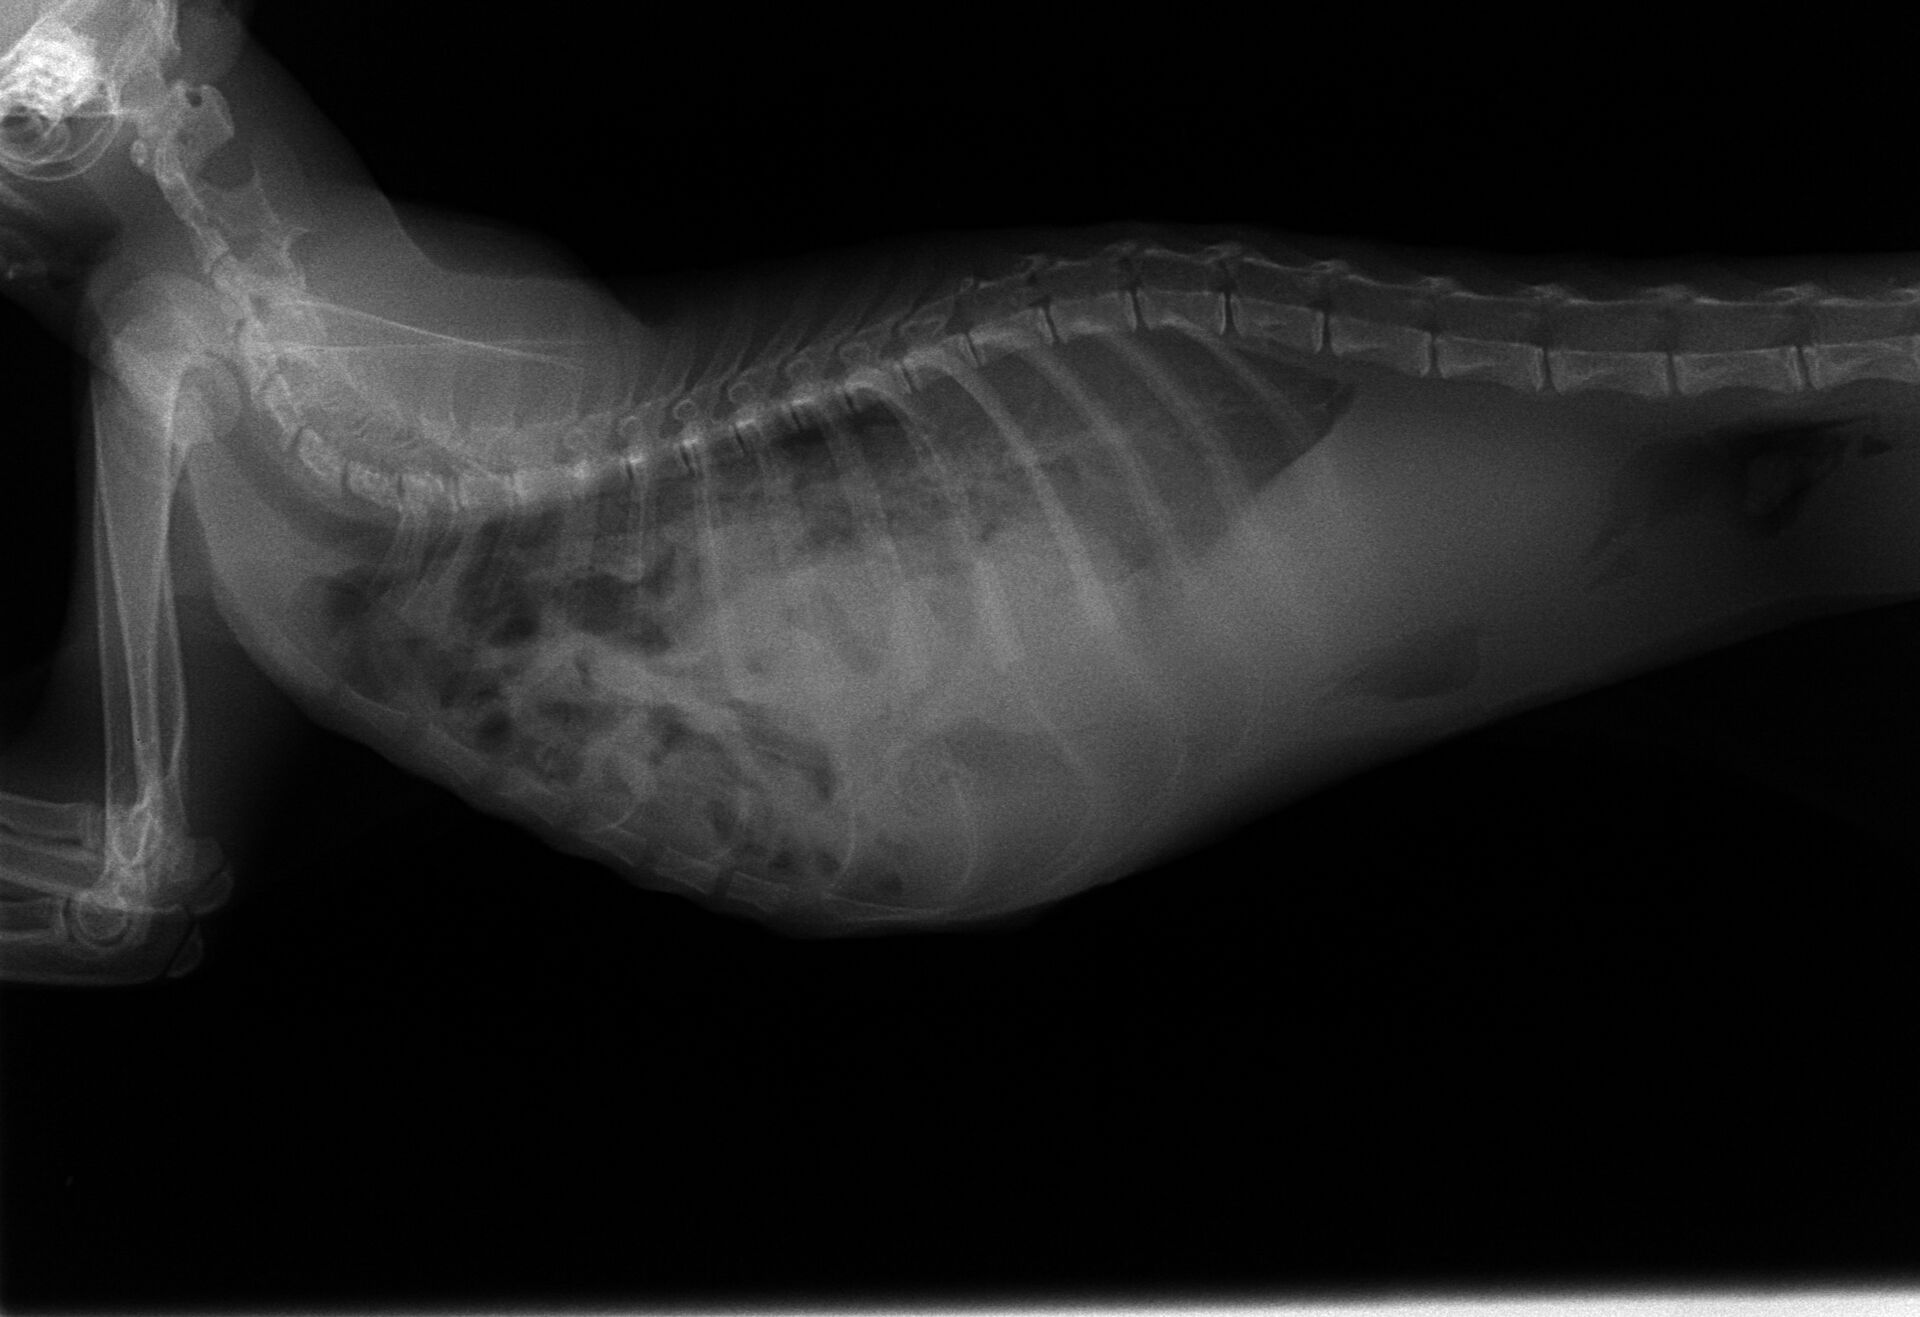

左右の横隔膜が破れていましたが、右側は肝臓がふたになって肺はほぼ損傷はありませんでした。左側はほとんどの臓器が入って肺は押しつぶされまったく機能していませんでした。

下の写真が術後のレントゲン写真です。左の肺は押しつぶされているのがわかります。術後の麻酔の醒めが極端に悪く、回復するか心配されました。翌日もよく寝ていましたが、徐々に回復の兆しは見えてきてました。